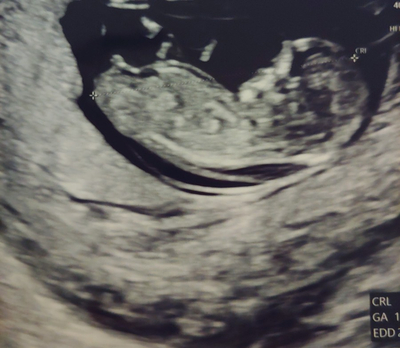

1.1차 정밀 초음파&통합 선별검사 임신 12주차는 중요한 시기로 아이가 많이 성장하여 배 초음파가 가능해져 1차 정밀 초음파검사와 통합 선별검사를 실시합니다.

정밀초음파는 1차(10~13주), 2차(20~21주)에 진행되는데, 1차 정밀초음파검사: 태아의 목 투명띠(NT) 두께 측정으로 태아의 염색체, 심장에 이상이 있는지 확인합니다.보통 2.5mm 미만이 정상입니다 (목 투명 대란, 아기를 둘러싼 양막에서 목까지의 빈 부분입니다)

2차 정밀 초음파 검사 : 태아의 성장(외형, 내부 장기 등)을 파악합니다.분만일 기준 만 35세 이상 산모, 이전 염색체 이상이 있는 아이를 임신한 산모 등 위험군이 아니라면 통상 통합 선별검사, 1차 2차 산모의 혈액검사를 통해 다운증후군 등 이상 유무를 파악합니다.하지만 직접적인 태아의 염색체를 확인하는 방법은 아니기 때문에 진단율은 90~94%이고 진단을 놓칠 가능성이 5~10%가 됩니다.